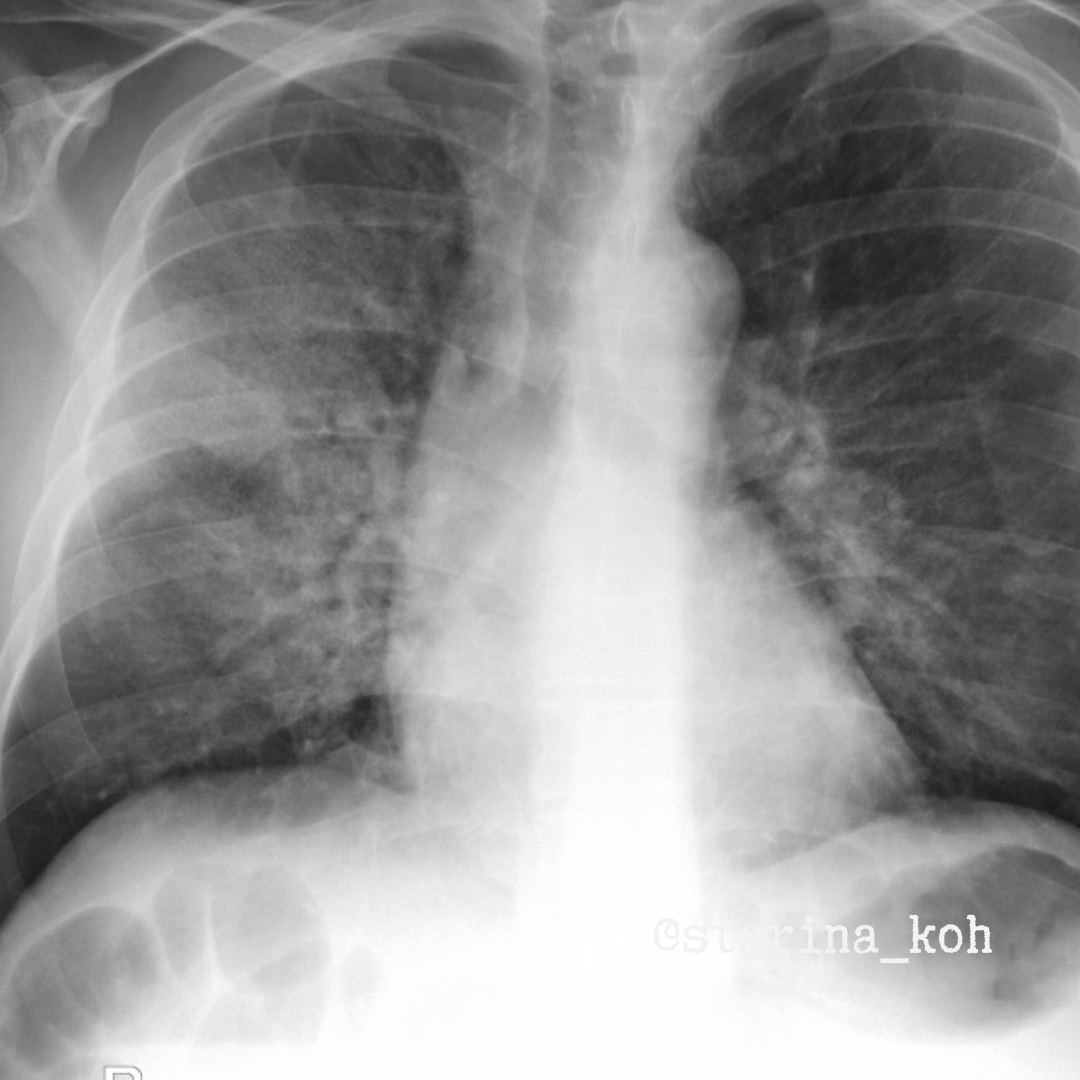

Дело происходит в декабре этого года, буквально неделю назад. Мужчина 48 лет поступил в хирургическое отделение из инфекционного стационара, где находился на лечении с диагнозом ОРВИ. ПЦР РНК nSARS CoV-2 отриц., IgG 739,5, IgM - до 2. Текущие жалобы: желтушность кожных покровов и неприятные ощущения в области дренажа брюшной полости. Отягощенный анамнез - с 1996 г. он страдает гепатитом С, злоупотребляет алкоголем с исходом в цирроз смешанного генеза. Из-за асцита пациенту установлен дренаж брюшной полости, через который ежедневно пациент самостоятельно спускает до 500 мл жидкости. На уровне приемного отделения: РГ ОГК - очаги и инфильтраты не выявлены, хрипы отсутствуют, ЧСС 18/мин, Sat02 99%. В анализах крови - WBC 9,4, Hb 101, общий белок 54 г/л, АЛТ 15, АСТ 67,8, общий билирубин 100,9, СРБ 8,4. Уже находясь в отделении хирургии через неделю после госпитализации пациент стал жаловаться на слабый кашель и повышение Т тела до 37,5 С. Выполнена контрольная РГ ОГК - затемнения не появились. За последующие 2 дня у пациента усилился кашель, появились эпизоды повышения Т до 38,3, появились затруднения в дыхании, Sat02 снизилась до 93% - повторная РГ ОГК: двусторонние затемнения низкой и средней интенсивности, после чего пациент через кабинет КТ был переведен в ОРИТ.

А что по данным КТ? Двусторонние неоднородные уплотнения "матового стекла", которые занимали обширный объём в легких, на их фоне - небольшие консолидации, местами утолщенный междольковый и внутридольковый интерстиций, малый двусторонний выпот в плевральных полостях - знакомая картина COVID-19, а по сути - любого вирусного повреждения в лёгких! В этот день выполнена повторная ПЦР на nSARS-COV2 и другие вирусы - и получили подтверждение наличия вируса гриппа H1N1! У пациента нарастала воспалительная реакция с повышением СРБ до 42,8 нг/мл, нарастал печеночный цитолиз (АСТ до 5100!), при этом прокальцитонин - N. Нарастание дыхательных жалоб потребовало перевода пациента на ИВЛ. К сожалению, несмотря на респираторную и лекарсвтенную поддержку пациент скончался через 4 дня после этиологической верификации на фоне клиники РДСВ. О чем этот пост? Мы перестали находится в рамках пандемии ковида и "матовое стекло" в лёгких с типичным расположением может оказаться результатом действия любого вируса (как стереотипная реакция в рамках диффузного альвеолярного повреждения), поэтому в заключениях достаточно указывать о вирусном характере подтверждения лёгких, а врачам-клиницистам - по возможности увеличивать распространенность этиологической верификации у пациентов с ОРВИ в непростой ситуации, когда ковид остается, но эпидемиологи указывают также и на рост гриппа, в т.ч. H1N1, который уже был причиной прошлой пандемии. Или вы видите разницу между повреждением лёгких при гриппе и ковиде? А ну-ка расскажите! ;)